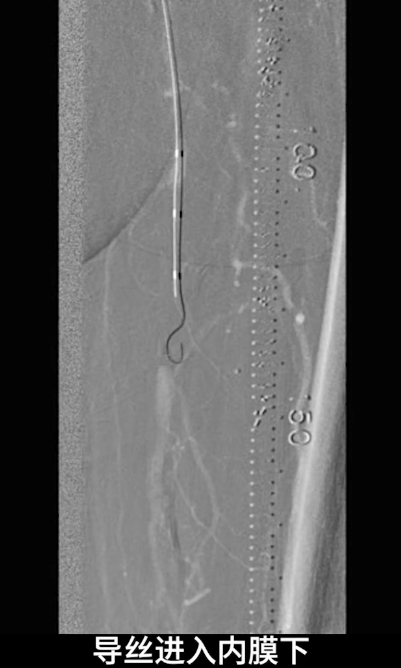

股浅动脉闭塞段开通

首先尝试顺行通过股浅动脉闭塞段,导丝进入内膜下,开通失败;遂改为逆穿策略,以支撑导管配合V18导丝逆行通过股浅动脉闭塞段,最终与近端股浅动脉真腔成功对接,建立安全操作轨道。

沿已建立轨道,选用4.0×150mm PTA球囊对股浅动脉闭塞病变段进行预扩张,为后续药物球囊治疗创造条件。